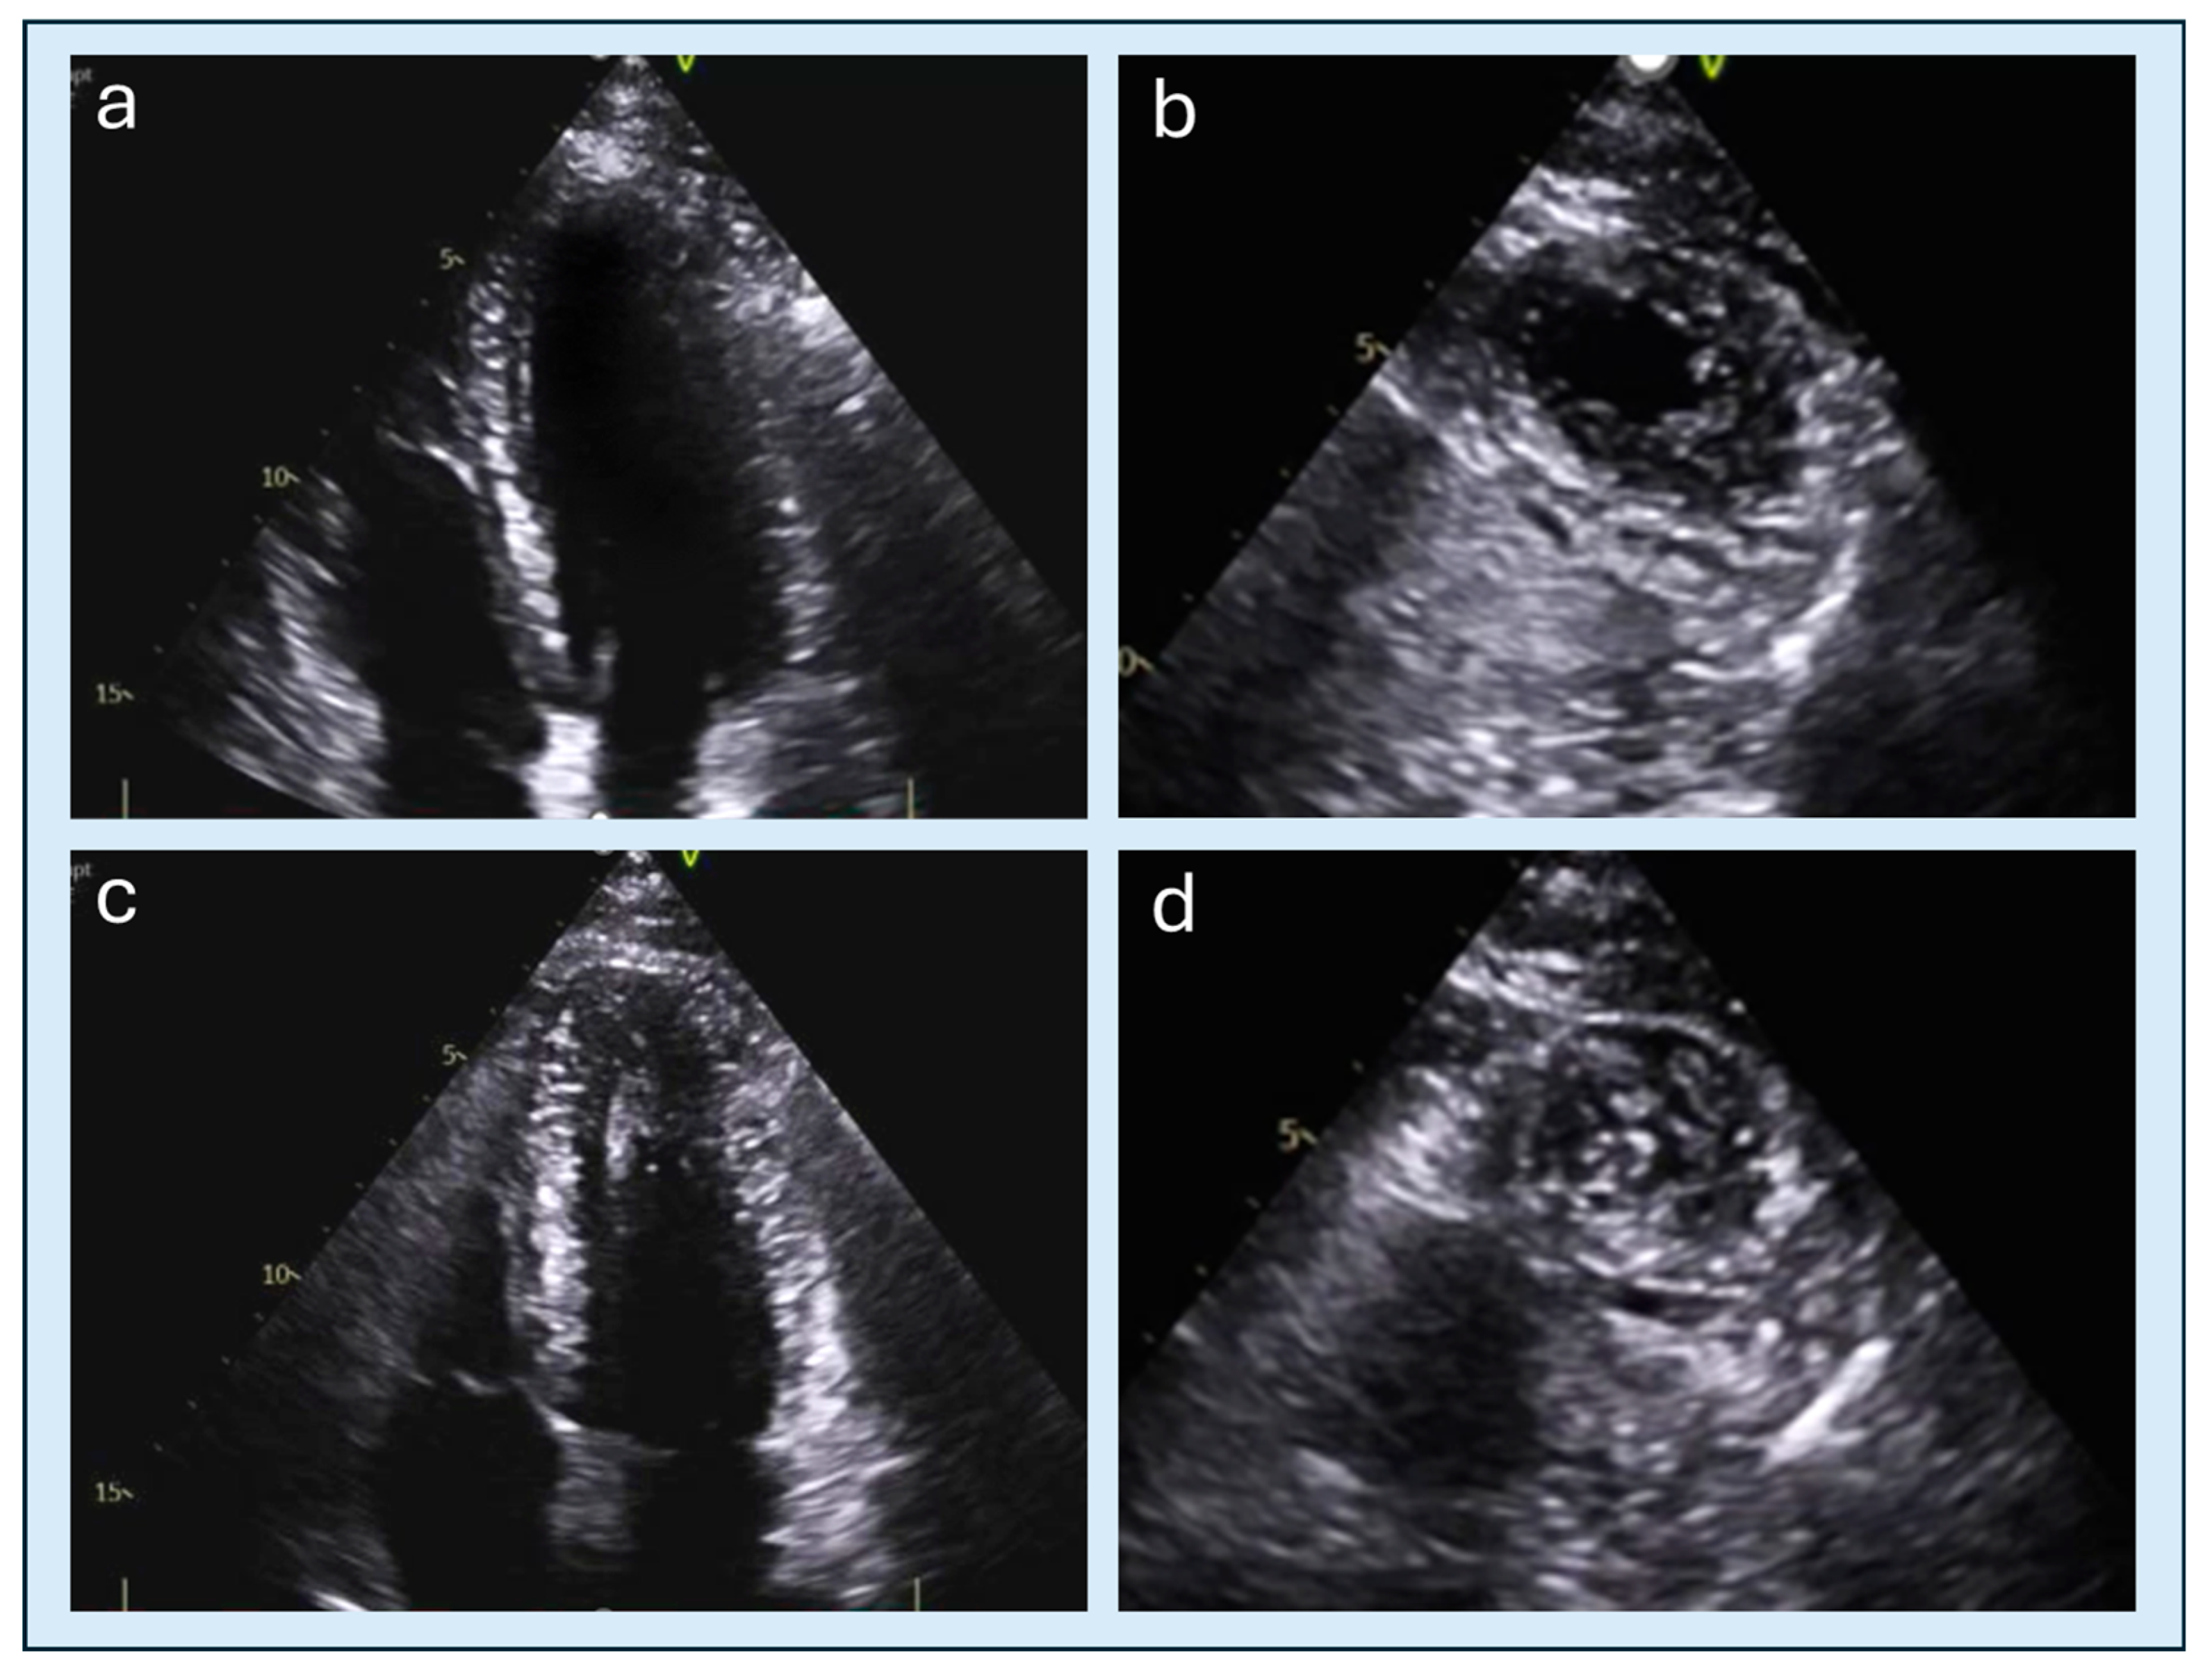

4.2. Apical Obliteration

| Echocardiographic Detection | Good sensitivity, especially for septal hypertrophy; color-Doppler useful for LVOT obstruction | Often underestimated without contrast; up to 43% of apical aneurysms may be missed by TTE |